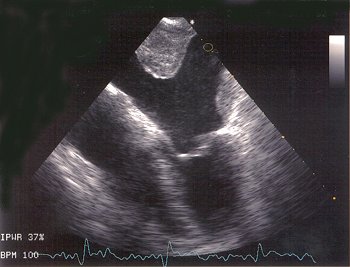

Sonde (rechts im Bild) in der Speiseröhre direkt hinter dem Herzen

Thrombus (Gerinnsel) im linken Herzvorhof